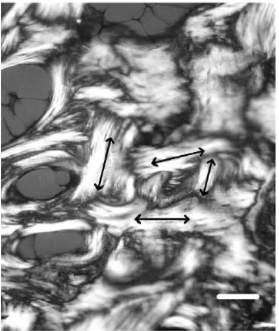

What type of bone is this?

Woven bone

Made quickly

Disorganised

No clear structure